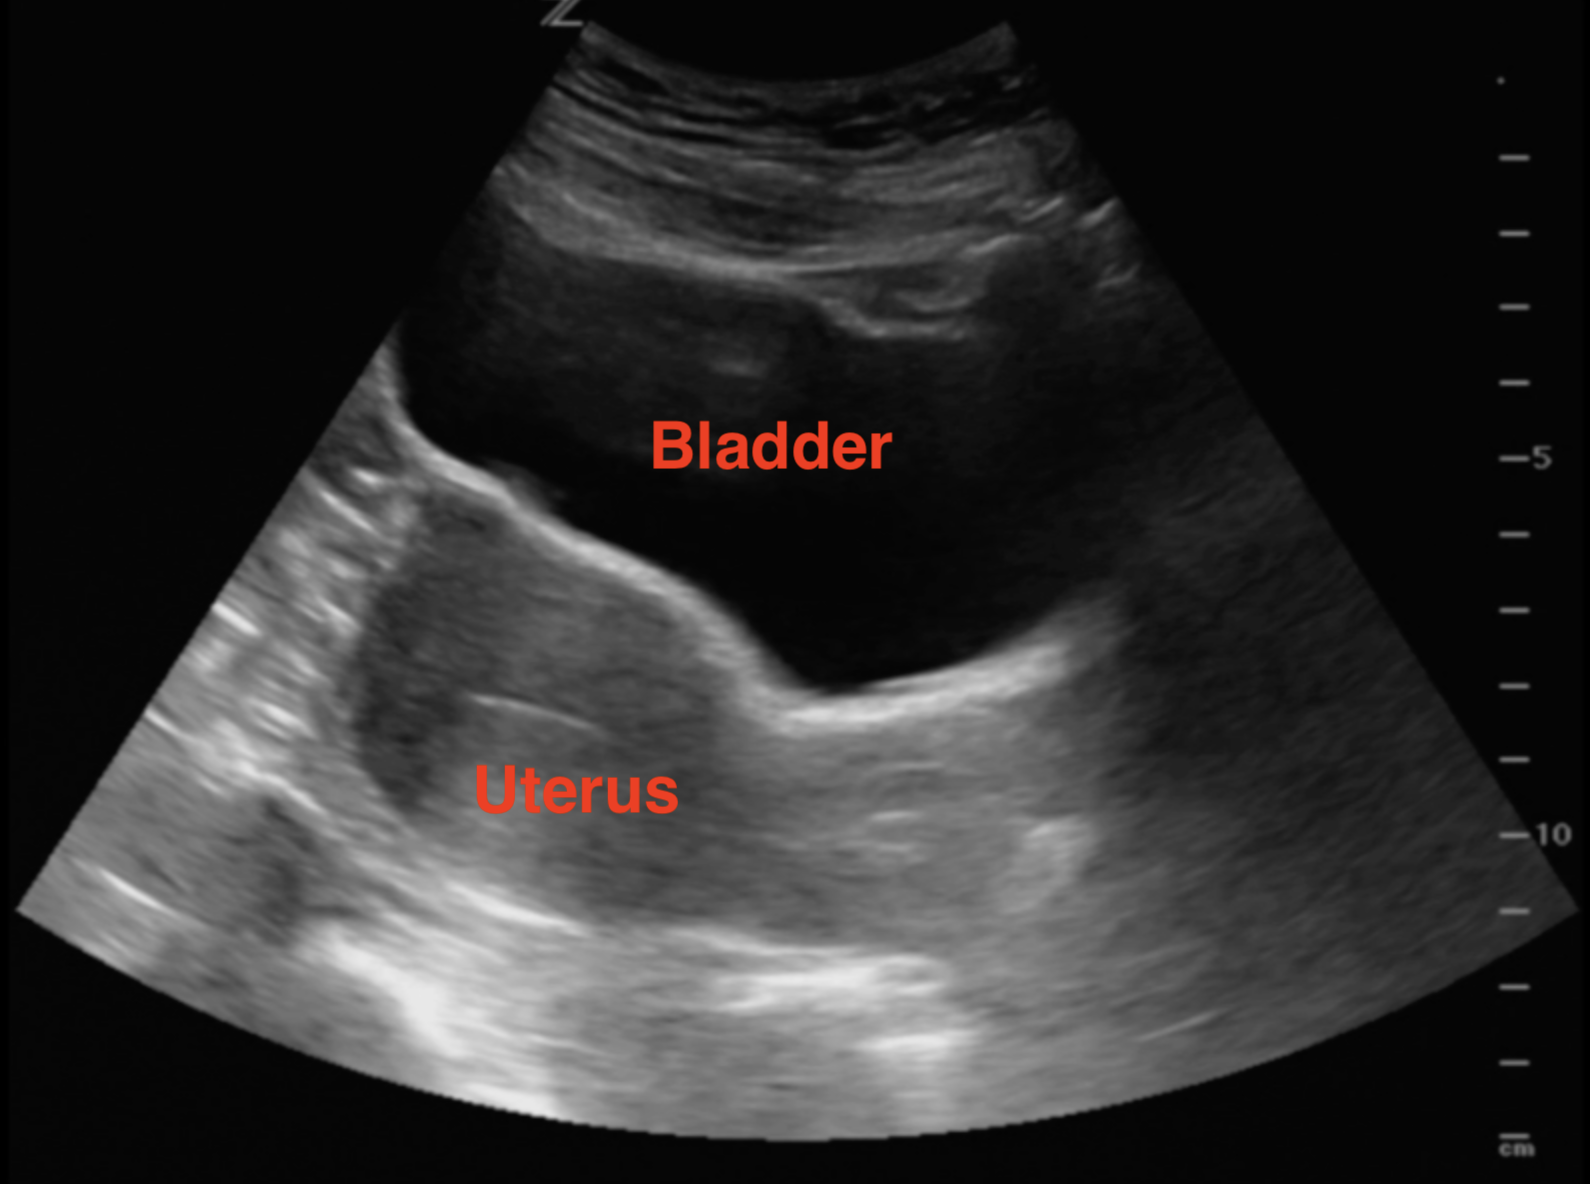

How to detect early miscarriage. How doctors diagnose miscarriage quantitative hcg blood test. A lab can examine the tissue to check for signs of a miscarriage. What is an early miscarriage and how common is it?

In most cases, an ultrasound scan can determine if you're having a miscarriage. The signs of early miscarriage will depend on the gestation of your pregnancy. It may feel crampy or persistent,.

Vaginal spotting or bleeding is usually the first sign of miscarriage. The uterus is a muscle, and it contracts during. Doctors describe an early miscarriage as one that happens in the first 12 weeks of pregnancy.

Call your doctor if you think you’re having a miscarriage. Detecting miscarriage is not always straightforward “a lot of people come in with bleeding and are justifiably nervous,” says dr. If these symptoms happen early enough—or if you haven't received a positive pregnancy test.